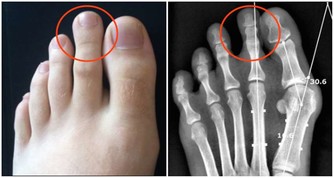

1、骨密度下降

35歲後人的骨質開始流失,進入自然老化過程,而絕經後女性的骨質流失更快。

骨質流失太快會出現骨質疏鬆,嚴重者重者容易出現骨折。

50歲以上的男性、45歲以上的女性是骨質疏鬆的高發群體。